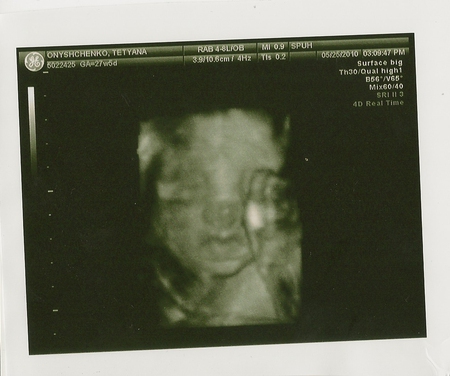

Сходили мы на УЗИ)Нам подтвердили дочу, да и еще крупным планом показали это самое с 4д эфектом) К моему удивлению УЗИ на 28 неделе включает и 4д просмотр бесплатно, я рада)) Показали мне моську нашего чуда, мои молитвы услышаны и моя умница послушалась маму и взяла мамин носик, а не папин шнобель))) А вот губки папины, и слава Богу, я от них без ума, и очень рада, что дочка взяла именно папины губки бантиком)) Правда очень напоминает деть меня в детстве))) Даже лоб большой тоже)) Все у нас хорошо, все показатели в норме, детка крупненькая, приблизительно 1 кг 215 грамм)) А вот мама козень, опять попала под раздачу врачей за недобор в килограмм)) Пофиг, главное, что джетка берет свое, а я... я уж как то потерплю без этого килограмма)))Главное что перебора нет))Так интересно было наблюдать как зевает моя детка)) Теперь НАКОНЕЦ-ТО я могу обращатся к дочке по имени, а не пупс,детка и тд! Огорчало одно, что наш папочка с нами не пошел, подлец, типа что я там буду делать? Родится и посмотрю, а там итак ничерта не видно (ну не знали мы, что нас будут смотреть в 4д), когда я сказала ему по телефону что он пропустил, он расстроился (так ему и надо, будет знать) но мы над ним сжалились и притащили ему фоток, все таки он старался,ювелир наш)))Зарочка, надеюсь ты меня слышишь, мы тебя очень любим и ждем!!!

А вот собственно и наша красотка))

Познакомтесь Павлиашвили Зарина Гурамовна собственной персоной))